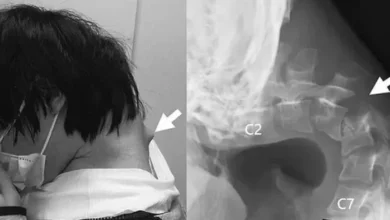

بسبب تصفح هاتفه.. شاب ياباني يصاب بمتلازمة “سقوط الرأس”

متابعة: بسنت عماد في واقعة غريبة تحمل رسالة قوية عن مخاطر الاستخدام المفرط للهواتف الذكية، أُصيب شاب ياباني يبلغ من…